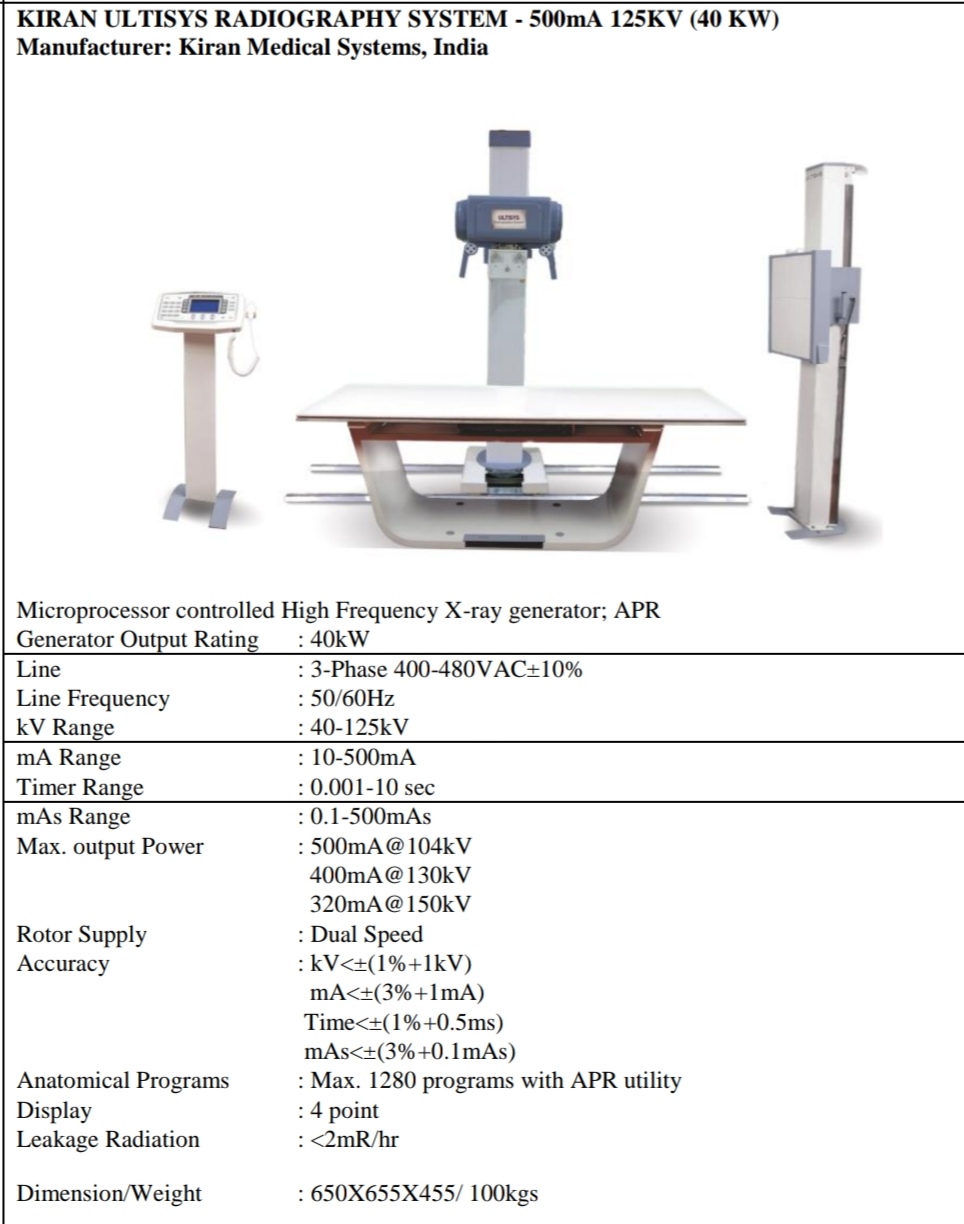

KIRAN ULTISYS RADIOGRAPHY SYSTEM - 500mA 125KV (40 KW)

KIRAN ULTISYS RADIOGRAPHY SYSTEM - 500mA 125KV (40 KW)